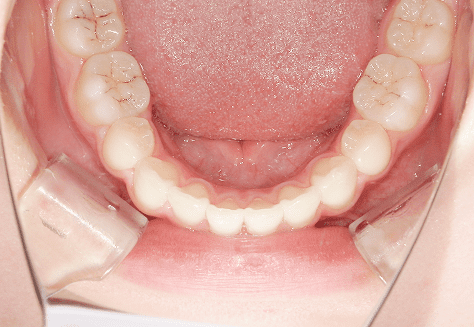

M.U

治療前

治療後

主訴

下の歯が特にガタガタなのが気になる。上の前歯が1本反対になっている。

診断

下顎前突・叢生・反対咬合

年齢/性別

20代/男性

抜歯部位

非抜歯

使用装置

上下インビザライン(PBM使用)

保定装置

ビベラリテーナー

料金

初回資料採得・・・・・・・30,000円

診断料・・・・・・・・・・33,000円

動的治療終了時資料採得・・5,500円 -

基本料金

950,000円

診察料金

5,500円×16回

治療期間

1年7カ月